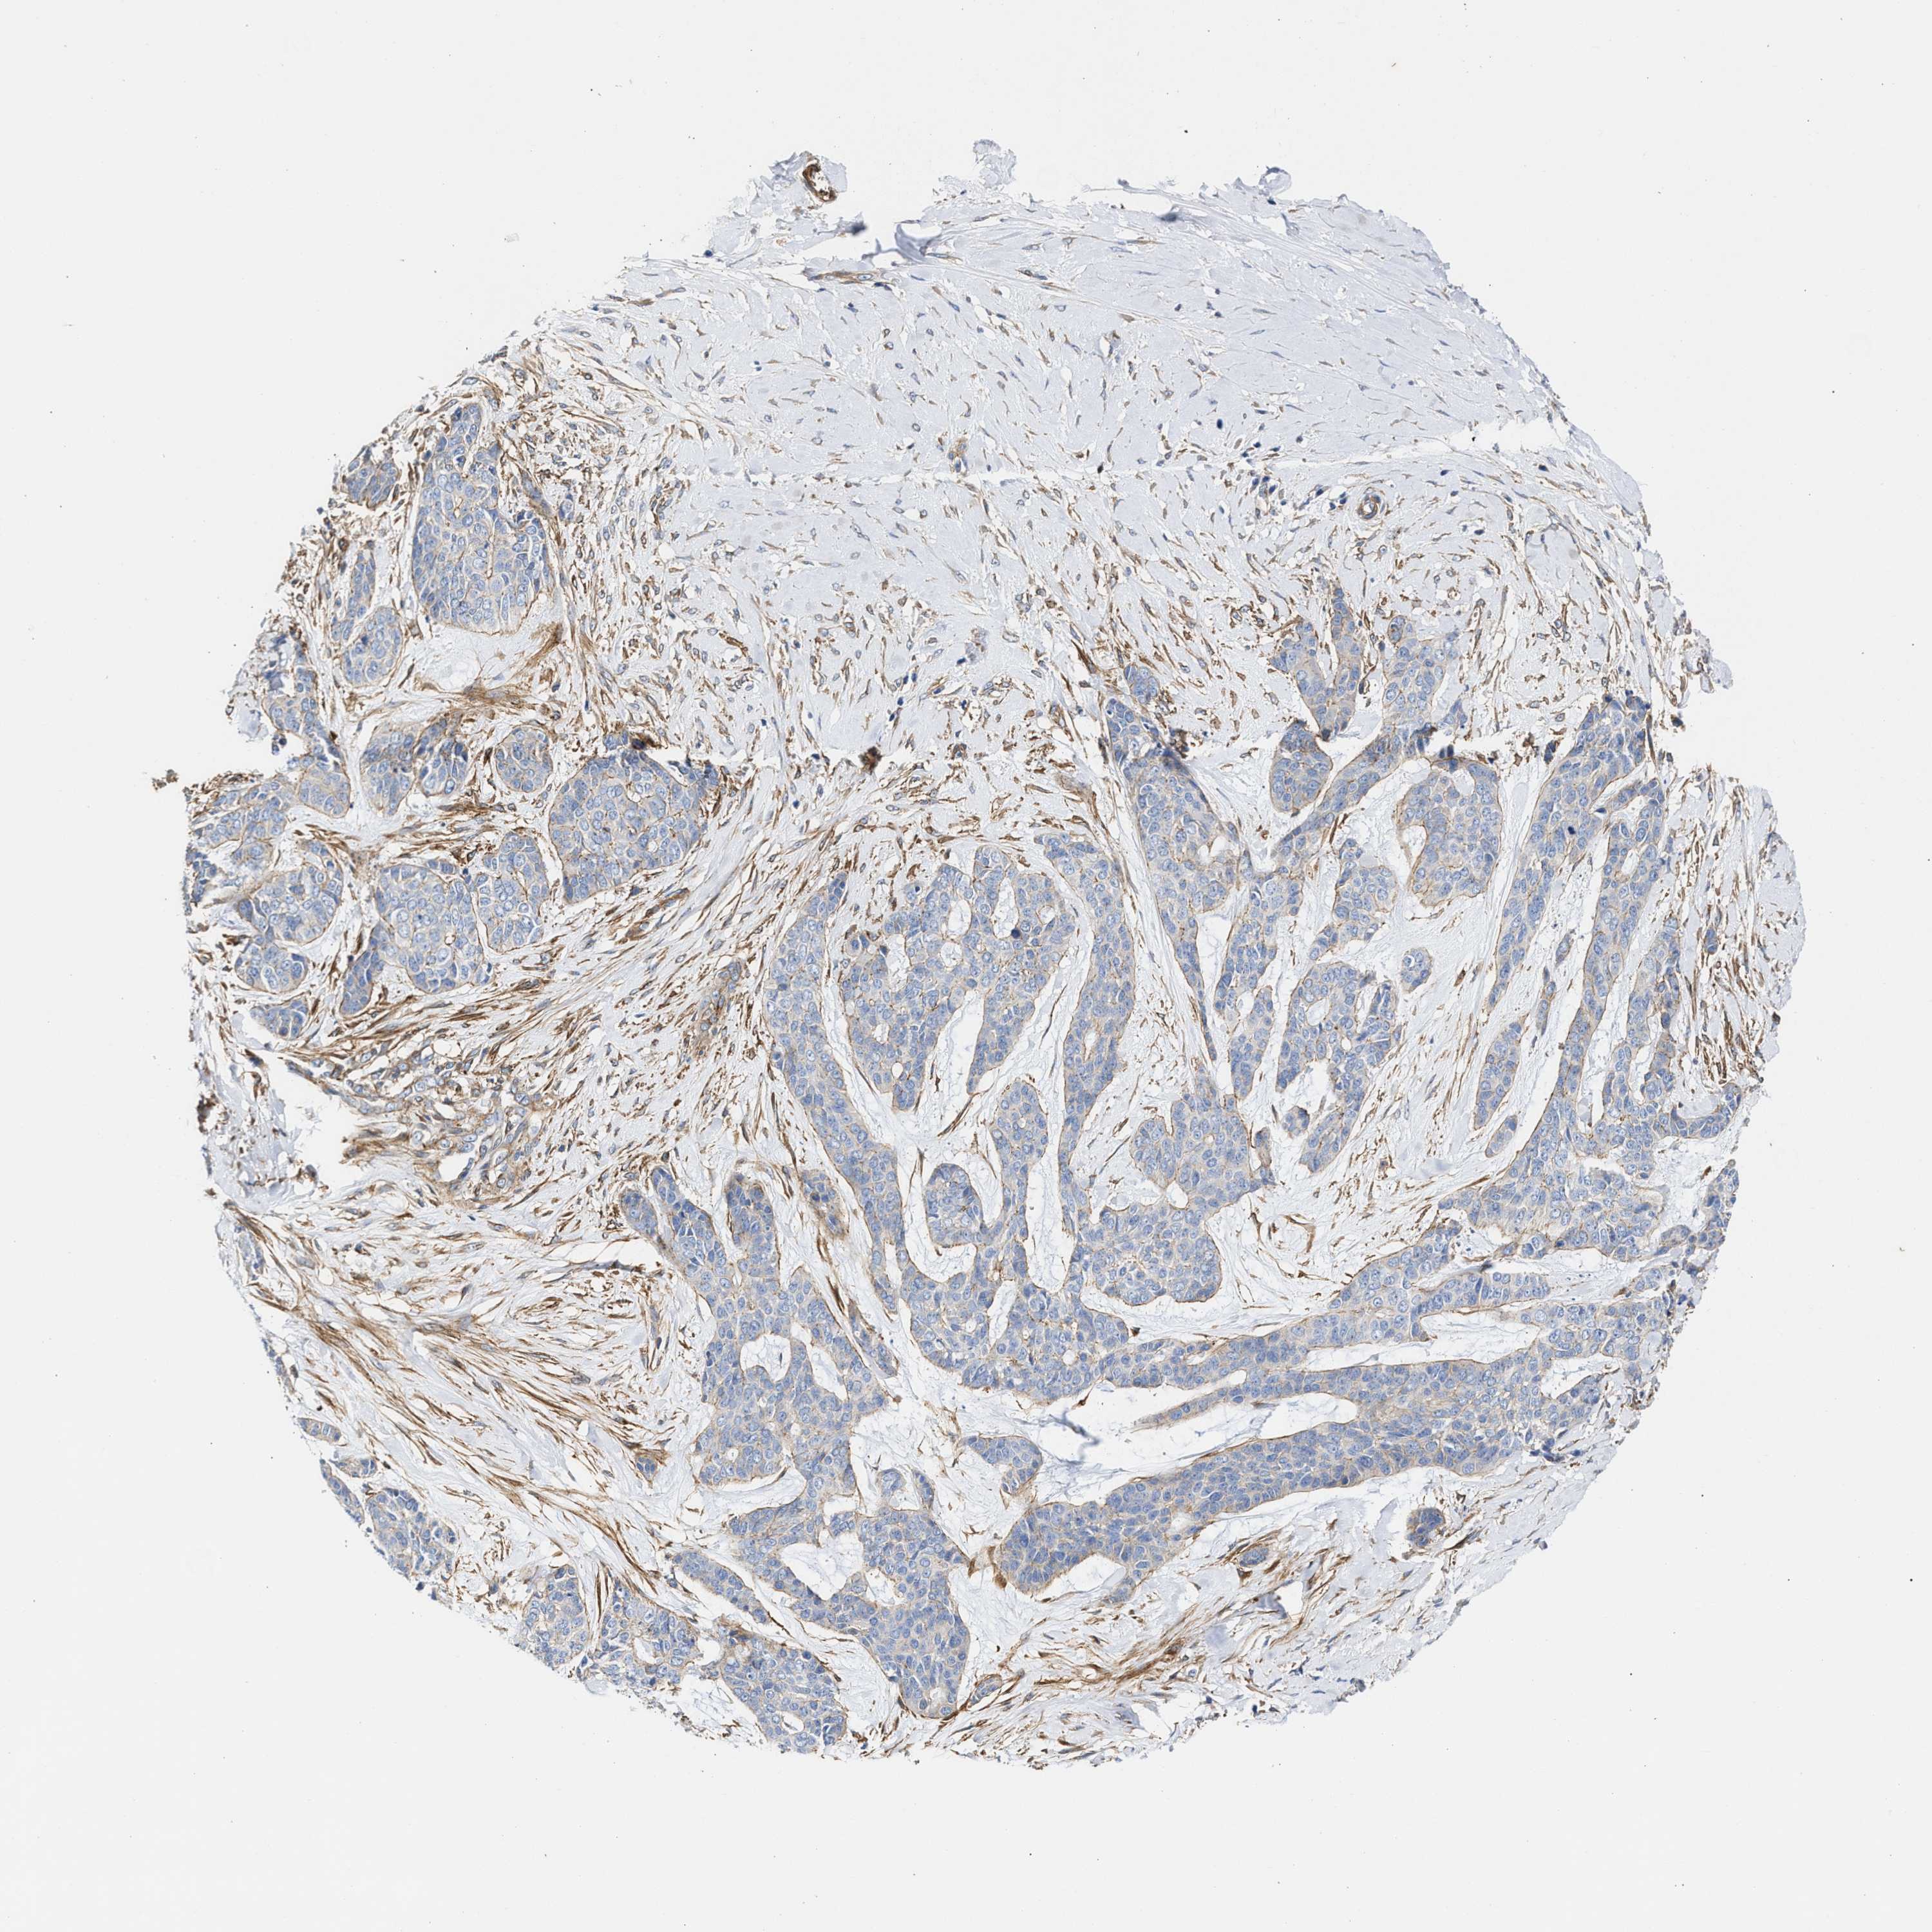

SKIN CANCER - Protein expressioni

A mouse-over function shows sample information and annotation data. Click on an image to view it in a full screen mode. Samples can be filtered based on level of antibody staining by selecting one or several of the following categories: high, medium, low and not detected. The assay and annotation is described here.

Antibody stainingi

Antibody staining in the annotated cell types in the current human tissue is reported as not detected, low, medium, or high, based on conventional immunohistochemistry profiling in selected tissues. This score is based on the combination of the staining intensity and fraction of stained cells.

Each image is clickable and will lead to virtual microscopy that enables deeper exploration of all samples and also displays staining intensity scores, fraction scores and subcellular localization as well as patient and tissue information for each sample.

Antibody HPA021823

Basal cell carcinoma

Squamous cell carcinoma, NOS

Squamous cell carcinoma, metastatic, NOS

BCC, high aggressive